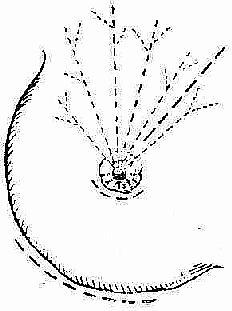

急性乳房炎脓肿形成期,治疗要则是及时切开引流,排出积脓。切开引流应注意如下要点:(1)为避免手术损伤乳管而形成乳瘘,切口应按轮辐方向作放射状切开,至乳晕处为止;深部脓肿或乳房后脓肿,可沿乳房下缘作弧形切口,经乳房后间隙引流之;既可避免乳管损伤,亦有利于引流排脓。乳晕下脓肿,应作沿乳晕边缘的弧形切口。(2)若炎症明显而未见波动处,不应消极等待,应在压痛最明显处进行穿刺,及早发现深部脓肿。(3)脓肿切开后,应以手指深入脓腔,轻轻分离其间的纤维间隔以利引流彻底。(4)为使引流通畅,可在探查脓腔时,找到脓腔的最低部位,别加切口作对口引流。(图2-12,2-13,2-14)。

图2-13 乳房脓肿的切口